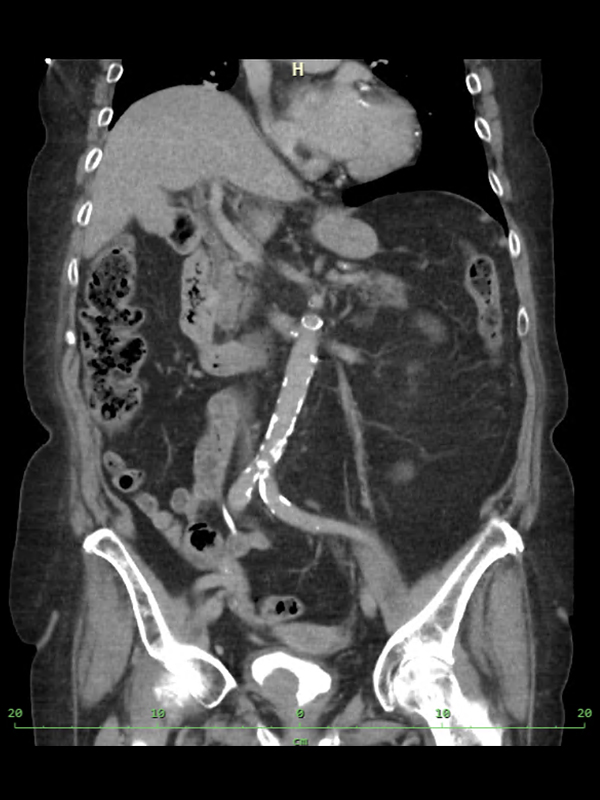

Radikální cystektomie je výkon, při kterém je odstraněn močový měchýř s odstraněním lymfatických uzlin za pomoci robotického systému Da Vinci Xi. Výkon se provádí u pacientů, u kterých byl diagnostikován pokročilý nádor močového měchýře (konkrétně takový, který prorůstá do svaloviny měchýře a zároveň se dosud nerozšířil na jiná místa v těle – nemá metastázy). Další skupinou pacientů, kteří jsou indikováni k tomuto výkonu jsou pacienti s endoskopicky neošetřitelným neinvazivním (povrchovým) nádorem a ti, kteří nereagují na lokální léčbu.

Jedná se o výkon v celkové anestezii, je nutná interní a anesteziologická předoperační příprava, vysazení léků na ředění krve v dostatečném předstihu. Operace probíhá v poloze na zádech, kdy se z několika malých řezů zavedou nástroje do dutiny břišní. Operatér ovládá nástroje z robotické konzole. Při operaci je nutné uvolnit měchýř od okolních tkání a cév, které jej zásobují krví. Oddělí se močovody a celý měchýř se odstraní. U mužů vyjmeme zároveň prostatu a semenné váčky, u žen je součástí operace odstranění vaječníků, dělohy a části pochvy. Dále je nutné vyřešit odvod moči z těla pacienta tzv. derivací moči.

Nejčastějším způsobem je tzv. ureteroileostomie. Operatér vybere vhodný úsek tenkého střeva který na dvou místech přeruší. Konce obou močovodů potom našije na jeden konec střeva, druhý konec střeva je vyveden ven na břišní stěnu vpravo od pupku, kde moč volně odtéká do nalepeného sběrného sáčku. Úsek střeva slouží jako prodlužovací potrubí mezi močovody a kožním vyústěním (stomií). Zbývající část střeva, která zůstala trávicímu ústrojí, se sešije, aby byla zachována jeho celistvost. Více informací o stomiích a práci stomických sester naleznete zde: (odkaz na Stomie)

Existuje možnost vyhnout se stomii. Ze zmíněného úseku tenkého střeva vytvoříme rezervoár, tzv. neoveziku, který uložíme na místo původního měchýře, přišijeme k původní močové trubici a močovody z ledvin našijeme na něj. Situace pak připomíná originální stav močového systému, kdy byl měchýř na svém místě. Tento operační zákrok je technicky náročnější, zatížený větším množstvím potenciálních komplikací a není zdaleka vhodný pro všechny pacienty.